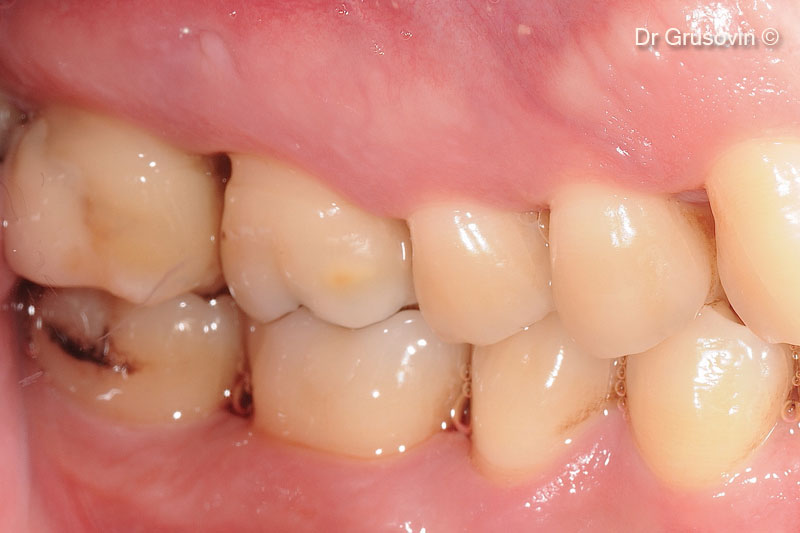

Bệnh nhân khỏe mạnh, không hút thuốc, hình ảnh lâm sàng trong miệng (vùng má).

Tăng số 16 quan trọng, tổn thương vùng chẻ nhánh III, vùng tiền đình xa